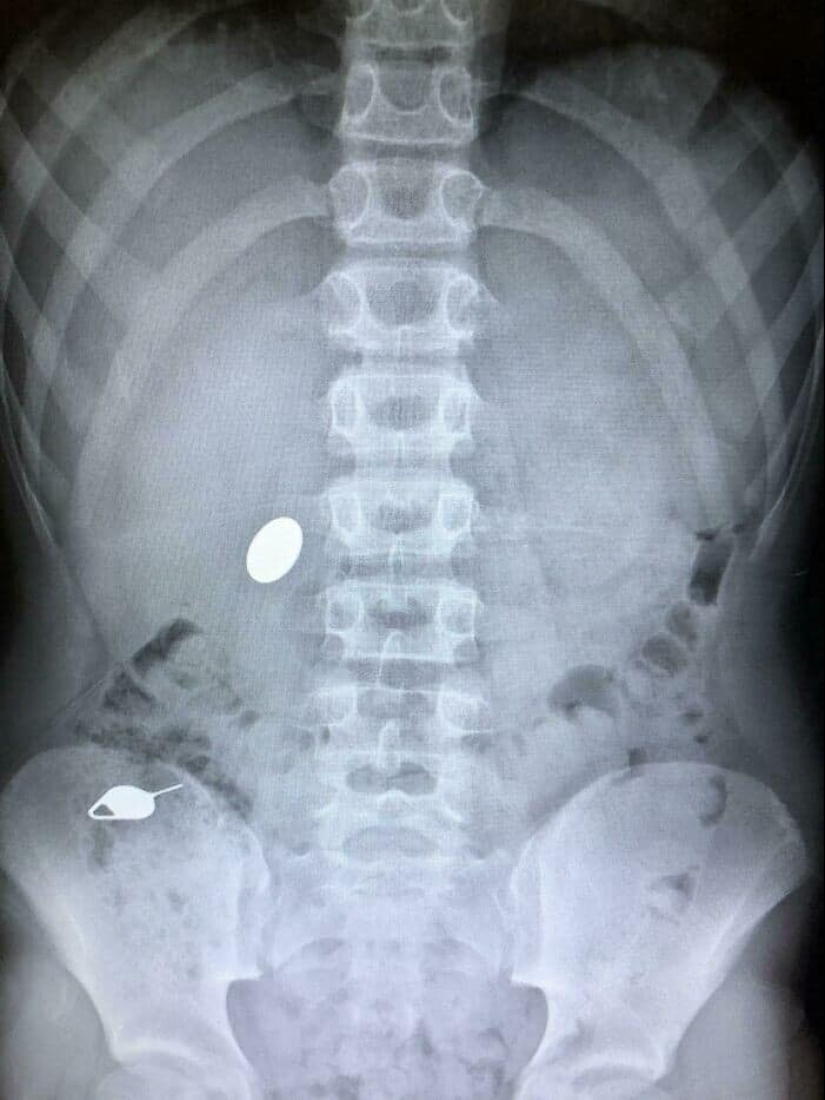

"Mi hijo se tragó una moneda mientras le mostraba a su hermano menor cómo se tragó accidentalmente la llave de la tarjeta SIM el día anterior"